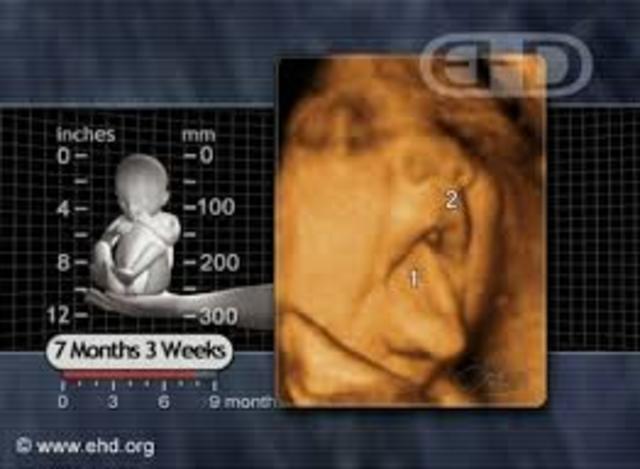

• 7 Months (Week 31-33)

7 Months (Week 31-33)

Week 31

Kicks and bumps will feel different

Week 32

As long as a kale leaf

Babies born at this time have a good chance of surviving

Fingernails and toenails are fully developed

Baby might even scratch his or herself if he or she gets an itch

Week 33

Size of a pineapple

Brain and nervous system are full development

Baby's skin is still continuing to smooth out and become less wrinkly

The white fat below baby's skin causes his or hers skin to be less red

Baby's skull is soft for the birth canal